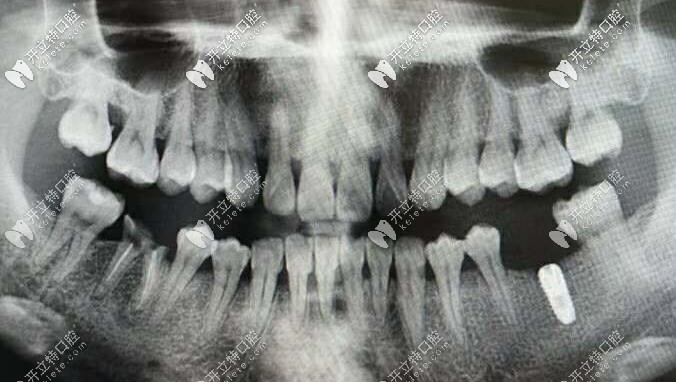

韓國(guó)inno種植體

韓國(guó)伊諾種植體種植體在近幾年內(nèi)慢慢進(jìn)入市場(chǎng),一經(jīng)使用便受到了廣大顧客的一致認(rèn)可。伊諾種植體是經(jīng)過(guò)了FDA、CE、CFDA等認(rèn)證的種植體,不管是安全性還是性能方面,都有著不錯(cuò)的表現(xiàn)。

伊諾種植系統(tǒng)

首先從材質(zhì)上看,inno種植體采用的是四級(jí)純鈦材質(zhì),尤其是自主研發(fā)的 Modi—ASD(改性陽(yáng)極氧化鈦)表面處理技術(shù),以其超親水和的骨結(jié)合效果令種植手術(shù)更加安全、穩(wěn)定。

這個(gè)材質(zhì)還有一個(gè)好處那就是——具備超親水特性及快速的骨結(jié)合速度。對(duì)于臨床病例如即刻植入、 即刻負(fù)重、上頜竇提升、植入深度調(diào)整都具有優(yōu)勢(shì)。

其次伊諾種植體還有多種不同的型號(hào),比如常規(guī)、超短、超窄、迷你(一段式)種植體,以及多樣化修復(fù)基臺(tái),能滿足口腔的各種修復(fù)需求。